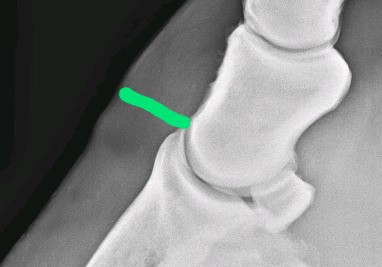

“Hovbenssänkning” mäts fram på en röntgenbild. Veterinären mäter avståndet mellan hovbenets övre kant och kronranden. För att korrigera för hästens storlek beräknas kvoten av det avståndet genom hovbenets längd. Kvoten bör inte överstiga 0,30 (Linford 1987).

Om kronranden är “för högt” ovanför hovbenet säger veterinären att hovbenet sjunkit. *